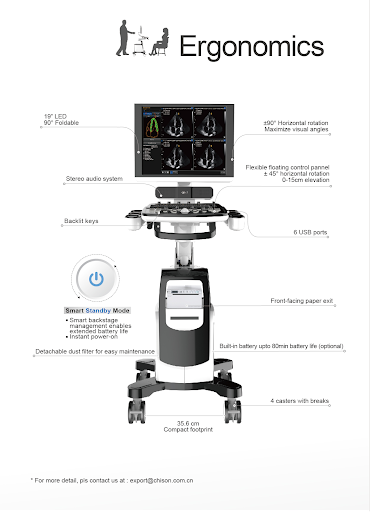

УЗИ аппарат с высокой мобильностью и эргономичностью обеспечивает комфорт для проведения исследования и оптимизирует рабочий процесс.

ЖК монитор 19 дюймов;

6 USB портов;

Встроенный аккумулятор. Время работы 80 минут (опционально).